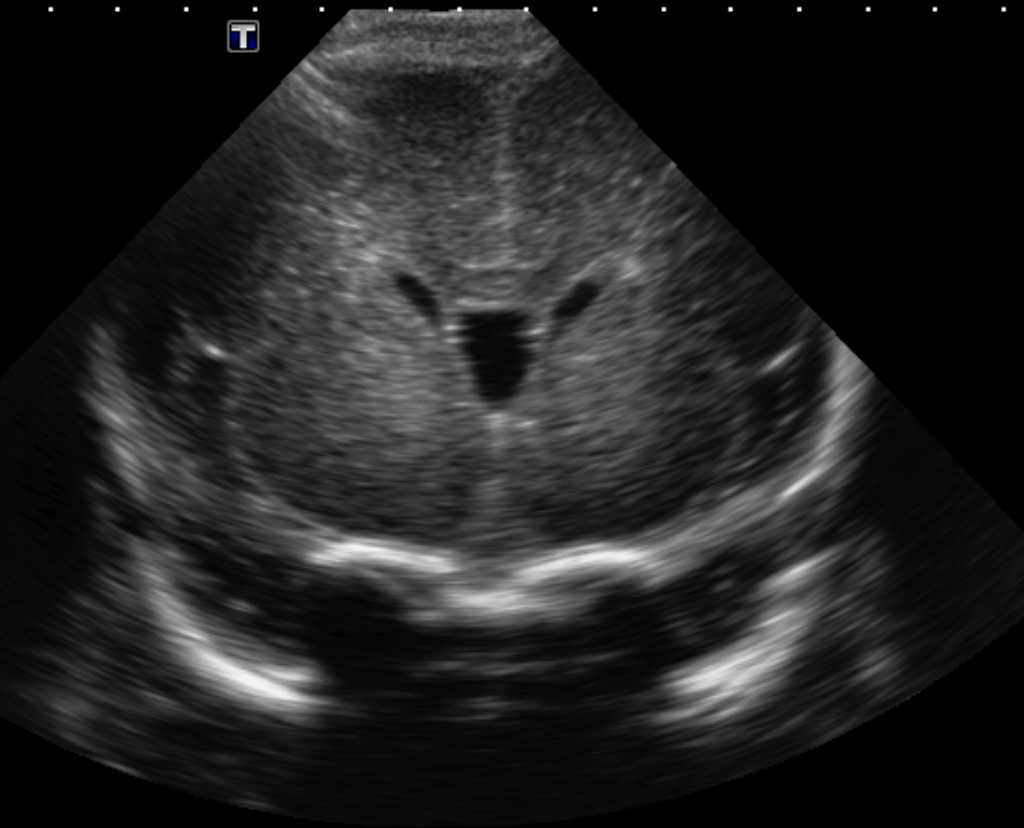

Info Images Findings Impression Reco/Acuity Case Images View Images / Launch Visage Case Notes History Full term infant. We are asked to evaluate posterior fossa cyst. Exam Gray scale and Doppler Ultrasonographic examination of the head. Prior Study N/A Dicom View Reference Material

Section 1 Submit Findings Case149 Findings Brain The brain is immature. Yes No There is under-sulcation and open sylvian fissures. Yes No There is/are multiple hypoechoic areas in the periventricular white matter. Yes No There is/are multiple hyperechoic areas in the periventricular white matter. Yes No There is diffuse cerebral edema with diffusely increased echogenicity of the brain parenchyma and loss of grey white matter differentiation. Yes No The thalami/basal ganglia are hypoechoic. Yes No There is periventricular calcification. Yes No There is intra-parenchymal calcification. Yes No CSF spaces/ventricular system There is a prominence of the extra axial fluid spaces. Yes No There are debris/septations in the extra axial fluid spaces. Yes No There are debris/septations in the ventricles. Yes No There is a subdural collection on the right/left side. Yes No There is prominence of the ventricular system. Yes No There is an asymmetry of the ventricular system. Yes No There is a cavum septum pellucidum. Yes No There is a midline shift towards right/left. Yes No The choroid plexus is bulky/lobulated. Yes No There is a choroid plexus cyst measuring… Yes No There are debris/clots in the occipital horn. Yes No There is a posterior fossa cyst measuring… Yes No The tentorium is elevated/depressed. Yes No The lateral ventricle/s are dilated. Yes No The third ventricle is dilated. Yes No The 4th ventricle is dilated. Yes No There are pseudo cysts. Yes No Germinal matrix hemorrhage (Only in the premature infants): Please do not answer if the patient is a full term. There is a germinal matrix hemorrhage, consistent with a grade I hemorrhage. Yes No There is an intraventricular extension consistent with a grade II hemorrhage. Yes No There is an intraventricular extension with the dilatation of ventricles, consistent with a grade III hemorrhage. Yes No There is an intra-parenchymal extension, consistent with grade IV hemorrhage. Yes No On color Doppler examination, the Resistive index in the anterior cerebral artery is… There is a loss of the diastolic flow on the Doppler exam. Yes No There is altered vascularity on Doppler imaging. Yes No There is an AVM in the region of… Yes No